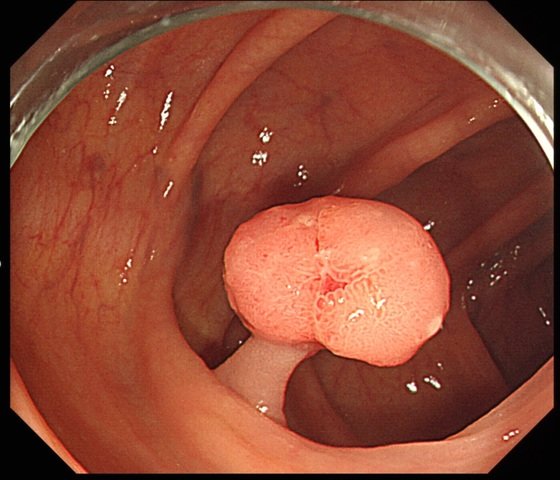

대장암은 대장내시경검사, 결장경검사 및 대변 기반 검사를통해 발견할 수 있어요. 대장내시경검사가 가장 철저한 선별검사 방법입니다. 끝에 카메라가 달린 길고 유연한 튜브를 사용하여 전체 결장과 직장을 시각화해요. 폴립이 발견되면 이 내시경이 진행되고 있는 도중에 제거할 수 있답니다.

대장내시경과 유사하게 결장경검사는 유연한 튜브를 사용하여 직장과 결장 하부를 검사해요. 그러나 결장 전체를 볼 수는 없답니다.